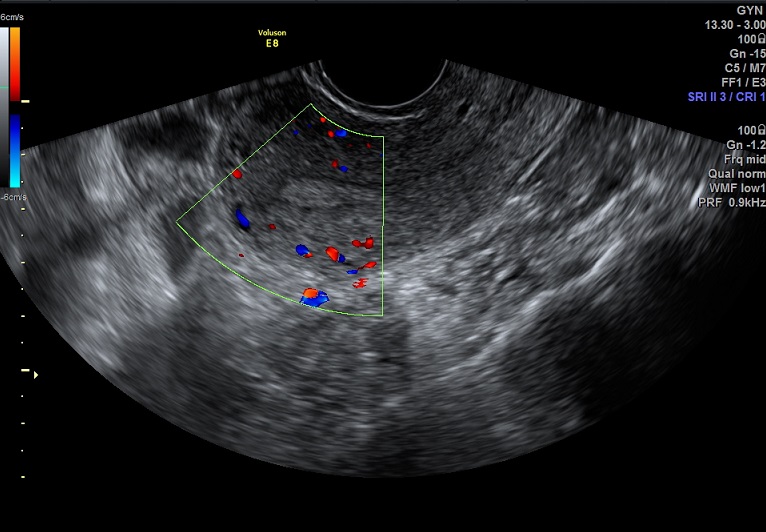

| 女性,25岁,继发性不孕1年余,难免流产4次。 | ||

2015-1-26 月经第23天检查 黄体期 |

2015-1-26图示